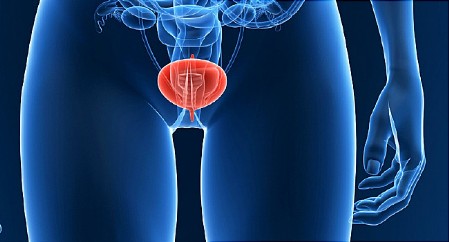

In termeni simpli UROLOGIA este specialitatea medico-chirurgicala care se ocupa de diagnosticarea si tratamentul afectiunilor sistemul urinar atat al barbatilor, cat si al femeilor si a sistemului reproductiv masculin.

In termeni simpli UROLOGIA este specialitatea medico-chirurgicala care se ocupa de diagnosticarea si tratamentul afectiunilor sistemul urinar atat al barbatilor, cat si al femeilor si a sistemului reproductiv masculin.

Sistemul genito-urinar este foarte complicat, exista multe domenii in care pot aparea probleme. Unele dintre aceste categorii includ: Infectii ale tractului urinar, Disfunctii sexuale si infertilitate, Cancer de prostata, Anomalii congenitale, Tumori genito-urinare, Traumatisme (in special in urma accidentelor), Operatie de reconstructie, Calculi renali sau "pietrele la rinichi", Uropatie obstructiva.

Incontinenta urinara, Vezica hiperactiva, Disfuncție sexuala feminina, cancer de vezica urinara.